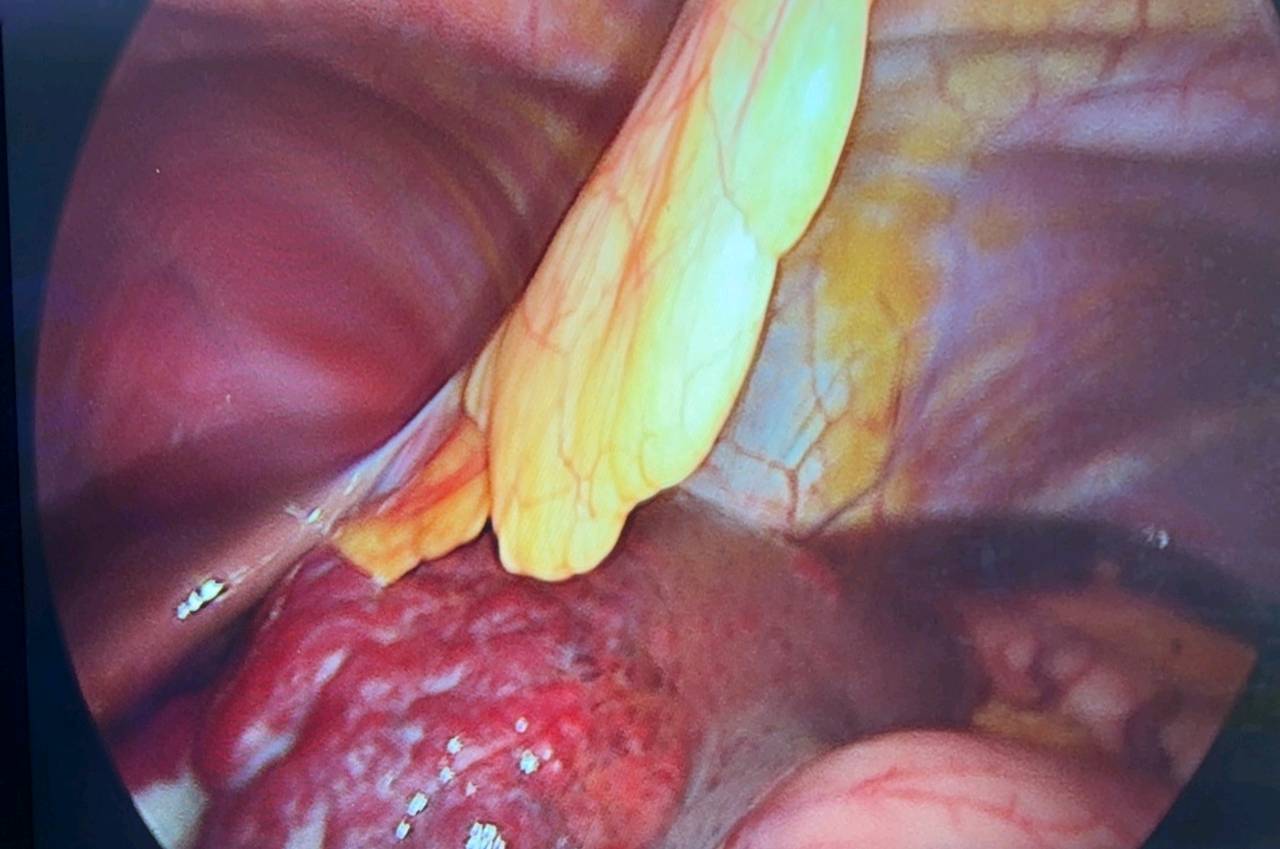

- 手术切除:适用于巨大血管瘤或位置特殊者。